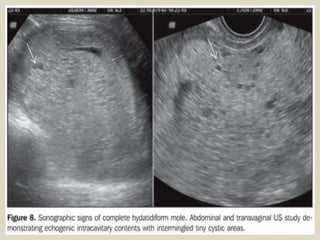

The gestational sac forms early in pregnancy to enclose an embryo and amniotic fluid. Certain sac characteristics can indicate a compromised pregnancy.

First-Trimester Ultrasound: Early Pregnancy Failure - First-Trimester Ultrasound: A Comprehensive Guide

Early Pregnancy Loss (Embryonic Demise) Imaging: Practice Essentials, Ultrasonography